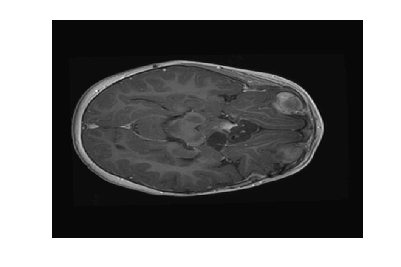

Figure 2: Image reconstruction from Case 20 (a, b, and c) and Case 3 (e, f, and g) of a brain image. Case 20 is the best performing algorithm that uses L1-W and case 3 is the best performing algorithm that uses LACS-MRI

The phantom image that we used in the previous experiment is flat and has less texture while the brain images has a lot of wrinkles and complex shapes. While the phantom image is small, the brain image is too large to calculate fNDsubscript𝑓𝑁𝐷f_{ND} efficiently. Thus, we conducted an experiment in the same setting as the phantom image excluding cases using fAsubscript𝑓𝐴f_{A}: cases 6 through 8 and 14 through 16. In this experiment, contrary to results for the phantom image experiment, L1-W performs better than LACS-MRI. For example, Case 3 performed the best among cases using LACS-MRI but it performs worse than 6 cases that use L1-W. Interestingly, one of the cases that shows an outstanding image recovery purely uses fVDSsubscript𝑓𝑉𝐷𝑆f_{VDS} with L1-W. However, purely using fVDsubscript𝑓𝑉𝐷f_{VD} with L1-W shows a dramatically worse performance. In conclusion, we are unsure why each combination of mixed PDFs and reconstruction algorithm perform differently based on the images processed, but this differing behavior is crucial to highlight for practical applications. We conjecture that the texture of the image is one factor that decides the performance of each algorithm. In the future, we may explore this conjecture and analyze why this happens.